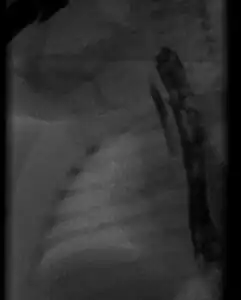

- Radiograph with oral contrast showing h-type tracheoesophageal fistula in a newborn